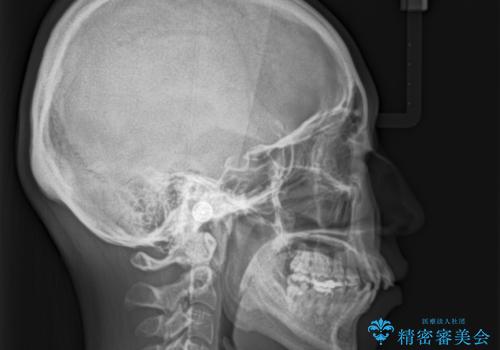

- 上下の出っ歯を気にして来院された患者様です。

口元を積極的に引っ込めるために、上下左右の第一小臼歯を4本抜歯することとしました。

最終的には上下の正中も合い、横顔の印象が変わるほどスッキリとした口元となりました。